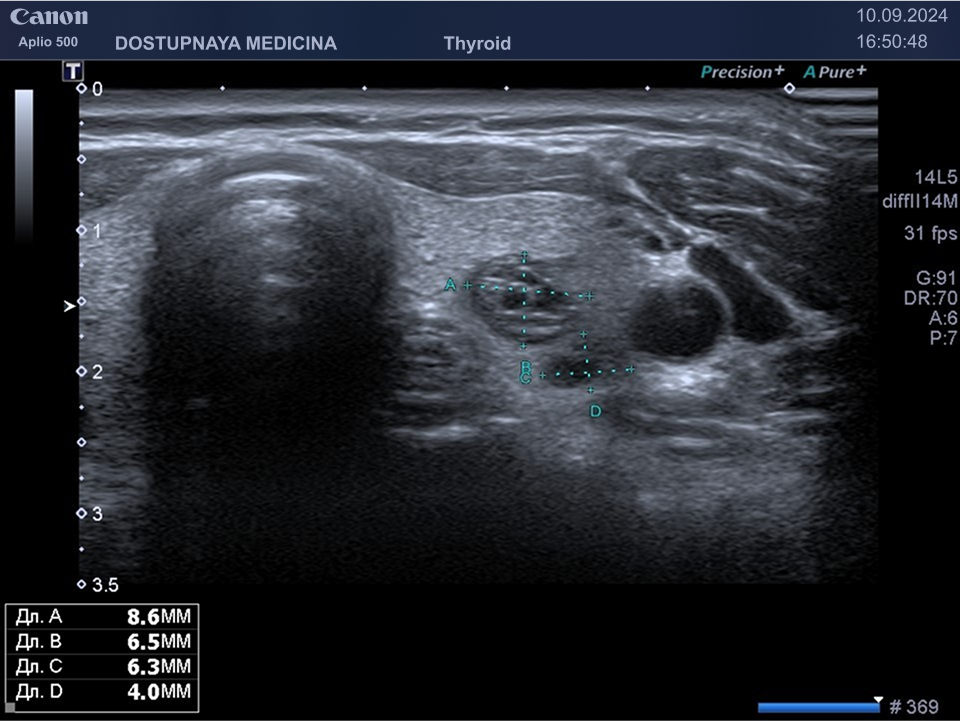

В ультразвуковой диагностике существует классификация образований щитовидной желзы по TIRADS, которая по различным критериям определяет степень онкоопастности того или ионого узла. При оценке учитывается эхоструткура образования ( кистозная, губчатая, солидная или солидно-кистозная), эхогенность ( анэхогенное, гиперэхогенное, гипоэхогенное), пространственная ориентация горизонтальная, вертикальная, неопределённая), контуры образования (ровные, дольчатые, зазубренные с острыми углами), наличие эхогенных включений( макрокальцинаты, микрокальцинаты, периферическая кольцевидная кальцификация). В зависимости от этих критериев выделяют различные категориии объёмных образований в щитовидной железе:

TIRADS 3 – низко подозрительное образование, требующие динамическое наблюдение и тонкоигольной биопсии при размерах узла больше 2.5 см.

TIRADS 4 – умеренно подозрительное образование, требующие динамическое наблюдение и тонкоигольной биопсии при размерах узла больше 1.5 см.

Большинство узловых образований в щитовидной железе не нуждаются в лечении и требуют лишь наблюдения путём повторного ультразвуковых исследований.

При подозрении на озлокачествление и увеличении узла в размерах требуется тонкоигольная пункционная биопсия с полседующим цитологическим исследованием, полученного материала.